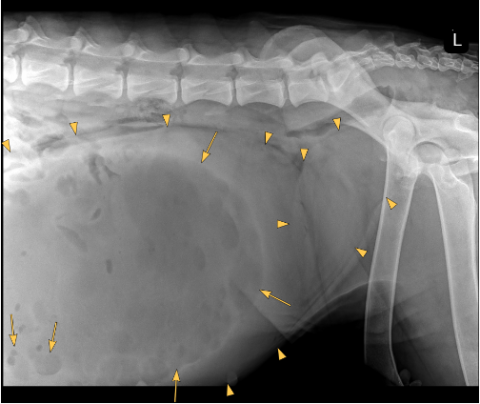

There is severe distention of the abdomen. As far as included the extra-abdominal soft tissues are within normal limits. There are 8 lumbar vertebrae, otherwise the bony structures are within normal limits.

A large well-defined, rounded soft tissue mass is noted in the caudal mid and cranial abdomen. The mass is filled with combination of fluid ( yellow arrow points) and gas (yellow arrows) and originating from the uterus.

The mass is displacing the gastrointestinal tract dorsally, cranially and laterally.

Large fluid and gas-filled mass in the caudal, mid and cranial abdomen originating from the uterus (emphysematous pyometra). Considering the shape of the mass a torsion is suspected.